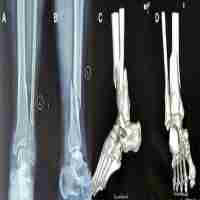

| Abstract | Purpose To determine the ideal entry point and direction of retrograde intramedullary nailing of the tibia. Methods The imaging data of patients with distal tibial fractures from June 2020 to December 2021 in our hospital were collected, and computer-aided design was performed. The relevant data were imported into the software for processing, so as to obtain a distal tibial fracture model and simulate the retrograde intramedullary nail placement in the tibia. The entry points and angles at which the intramedullary nail could be inserted successfully and the fracture could be maintained in good alignment were overlapped and counted to obtain the safe entry range and angle. The center of this safe range is the ideal entry point for retrograde intramedullary nailing of the tibia, and the mean value of the angle is the ideal direction of entry. Results The ideal entry point of the retrograde intramedullary nailing was located at the midpoint of the medial malleolus in the C-arm fluoroscopic anteroposterior (AP) and lateral view. The ideal nail entry direction was located at the anatomic axis of the medial malleolus in the AP position and at the anatomic axis of the distal tibial metaphysis in the lateral position. Conclusion The ideal point and direction of nail insertion for retrograde tibial intramedullary nailing is a \"double midpoint, double axis\" approach. |